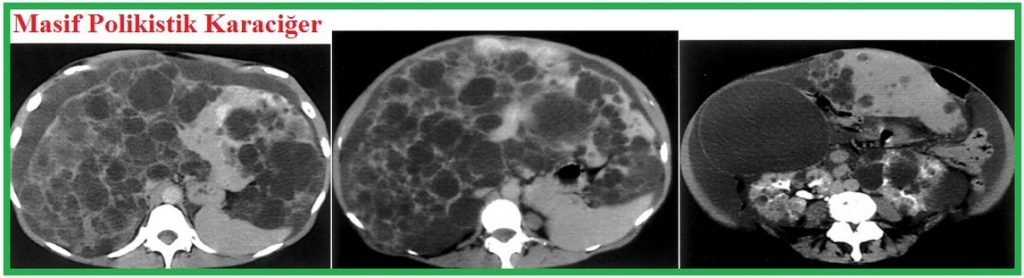

Renal bulgular: böbrek kistleri, nefrolitiazis, üriner sistem infeksiyonu, hipertansiyon, böbrek yetersizliği. Ekstrarenal bulgular: pankreas kistleri, kolon divertikülleri, herniler, dalak kistleri, intrakranial anevrizmalar, mitral kapak prolapsusu, karaciğer kistleri.

Ekstrarenal bulgular: Kistik bulgular: karaciğer (en sık karşılaşılan ekstrarenal bulgudur, karaciğer fonksiyon bozukluğuna yol açmaz), pankreas, dalak, seminal vezikül, araknoid. Nonkistik Bulgular: mitral kapak prolapsusu, anevrizmalar, kolon divertikülleri, herniler (inguinal, insizyonel, paraumbilikal).

Pankreas kistleri % 10-15, dalak kistleri % 6-10 görülür.